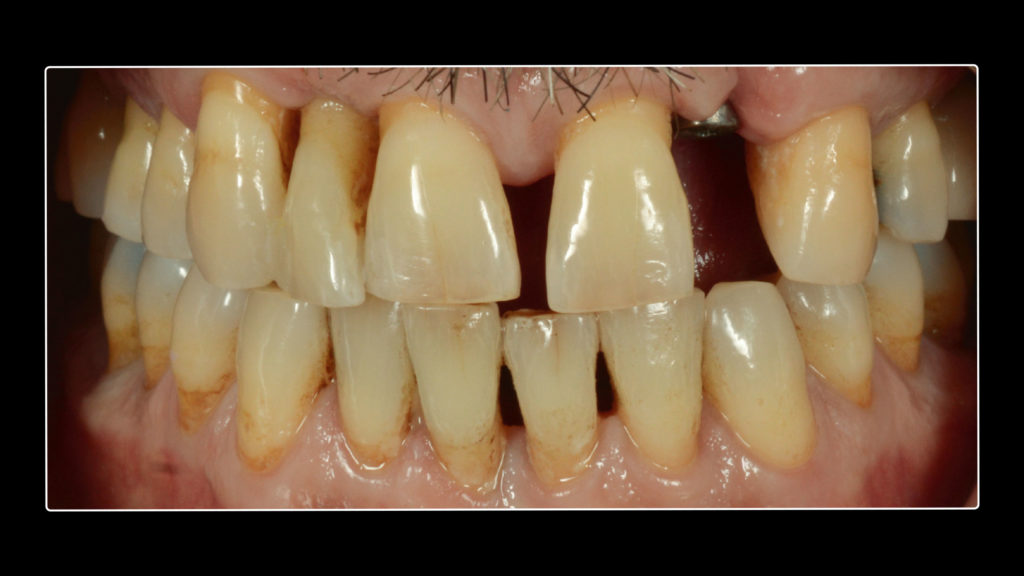

Bei dem Patienten handelte es sich um einen 49-jährigen Mann, Raucher (mehr als eine Packung pro Tag), mit einer Parodontalerkrankung, die vor drei Jahren diagnostiziert und behandelt worden war. Er wurde wegen des plötzlichen Verlusts seines Zahns 25 in der Klinik vorstellig. Im Rahmen der Untersuchung wurde zudem ein Mobilitätsgrad 3 an Zahn 22, aber auch an Zahn 12 konstatiert. Um den fehlenden Zahn 25 zu ersetzen, wurde ein Implantat in Betracht gezogen. Im Verlauf der weiteren klinischen Untersuchung wurden harte und weiche Konkremente und drei Amalgamfüllungen festgestellt. Ein näheres Screening und die Sondierung ergaben, dass weder Parodontaltaschen noch eine aktive Parodontalerkrankung vorlagen. Der Patient wurde über seine Situation informiert und eine Panoramaröntgenaufnahme angefertigt (siehe Abb. 1). Um zusätzlich zu prüfen, ob eine Implantation risikofrei durchführbar wäre und wie es um die Prognose bestellt sein würde, war auch eine DVT indiziert. Zudem wurde der Patient über die Risiken des Rauchens und die damit verbundenen möglichen Komplikationen sowie den Status der Parodontalanamnese aufgeklärt. Die Panoramaröntgenaufnahme zeigt die Merkmale einer älteren parodontalen Vorerkrankung. Die Alveole des Zahns 22 wies keinen Kontakt zum Knochen und Zahn 12 nur noch Knochen um den Apex herum auf (Abb. 1). Bei der Auswertung der DVT-Aufnahme wurde hinsichtlich der Länge und Breite ein gutes Knochenangebot für eine Implantation festgestellt, sodass der Zahn 22 extrahiert und in dieser Region implantiert werden konnte. Es wurde daher beschlossen, neben dem Zahn 25 – wegen dessen Verlusts der Patient die Praxis ursprünglich konsultiert hatte – auch den Zahn 22 implantatprothetisch zu rekonstruieren. Die prothetische Herausforderung im ästhetisch sichtbaren Bereich ist der Grund dafür, in diesem Artikel lediglich die Versorgung des Implantats in regio 22 zu beschreiben. Inseriert werden sollte dort ein Sweden & Martina Premium One-Implantat mit einem Durchmesser von 4,25 und einer Länge von 11,5 mm. Für ein bestmögliches Implantationsergebnis wurde das Implantat sofort nach der Extraktion des hochmobilen und als nicht erhaltungswürdig eingestuften Zahns 22 inseriert. Die Vorteile der Sofortimplantation wurden erstmals von Prof. Dr. Willi Schulte von der Universität Tübingen beschrieben. Der verbliebene Raum zwischen der Extraktionsalveole und dem Implantat wurde mit einer anorganischen porcinen Knochenmineral-Matrix (MinerOss XP, Camlog) mit dem Volumen 0,5 aufgefüllt. In der Abbildung 2 ist die Situation nach Insertion des Schweden & Martina Premium One-Implantats dargestellt. Nach vier Monaten Einheilzeit waren die Gewebe bereit und der Patient konnte definitiv versorgt werden.

Nach dem Einheilen des Implantats fertigte der behandelnde Zahnarzt Aufnahmen der Situation mit einer DSLR-Kamera an und nahm Abformungen. In dieser Sitzung fotografierte er die Zähne auch mit vorgehaltenen Farbmusterzähnen und sendete alle Fotografien sowie die Abformungen an das Labor. Im Labor wurden die Fotos und Abformungen sowie die darin enthaltenen Informationen benötigt, um eine möglichst „unsichtbare“ implantatprothetische Versorgung herstellen zu können.

Auf Wunsch des Patienten sollte der zu rekonstruierende laterale Schneidezahn die Charakteristika des mittleren Inzisiven 21, also seines direkten Nachbarzahns aufweisen. Normalerweise hätte man sich an dem noch verbliebenen lateralen Schneidezahn im ersten Quadranten orientiert, doch leider war auch dessen Zustand nicht ideal, sodass auch dieser in Bälde rekonstruiert werden sollte (Abb. 7a und b). Bei der eingehenden Betrachtung des Zahns 21 stellten wir zwar eine gewisse Ähnlichkeit mit den vom Zahnarzt gewählten Farbmusterzähnen fest, erkannten aber auch relevante Unterschiede. Aus diesem Grund starteten wir die laborseitige Analyse mit polarisierten Aufnahmen (Abb. 8a und b). Da der Patient 49 Jahre alt war, suchten wir gezielt nach charakteristischen Merkmalen natürlicher älterer Zähne und und wurden auch fündig.